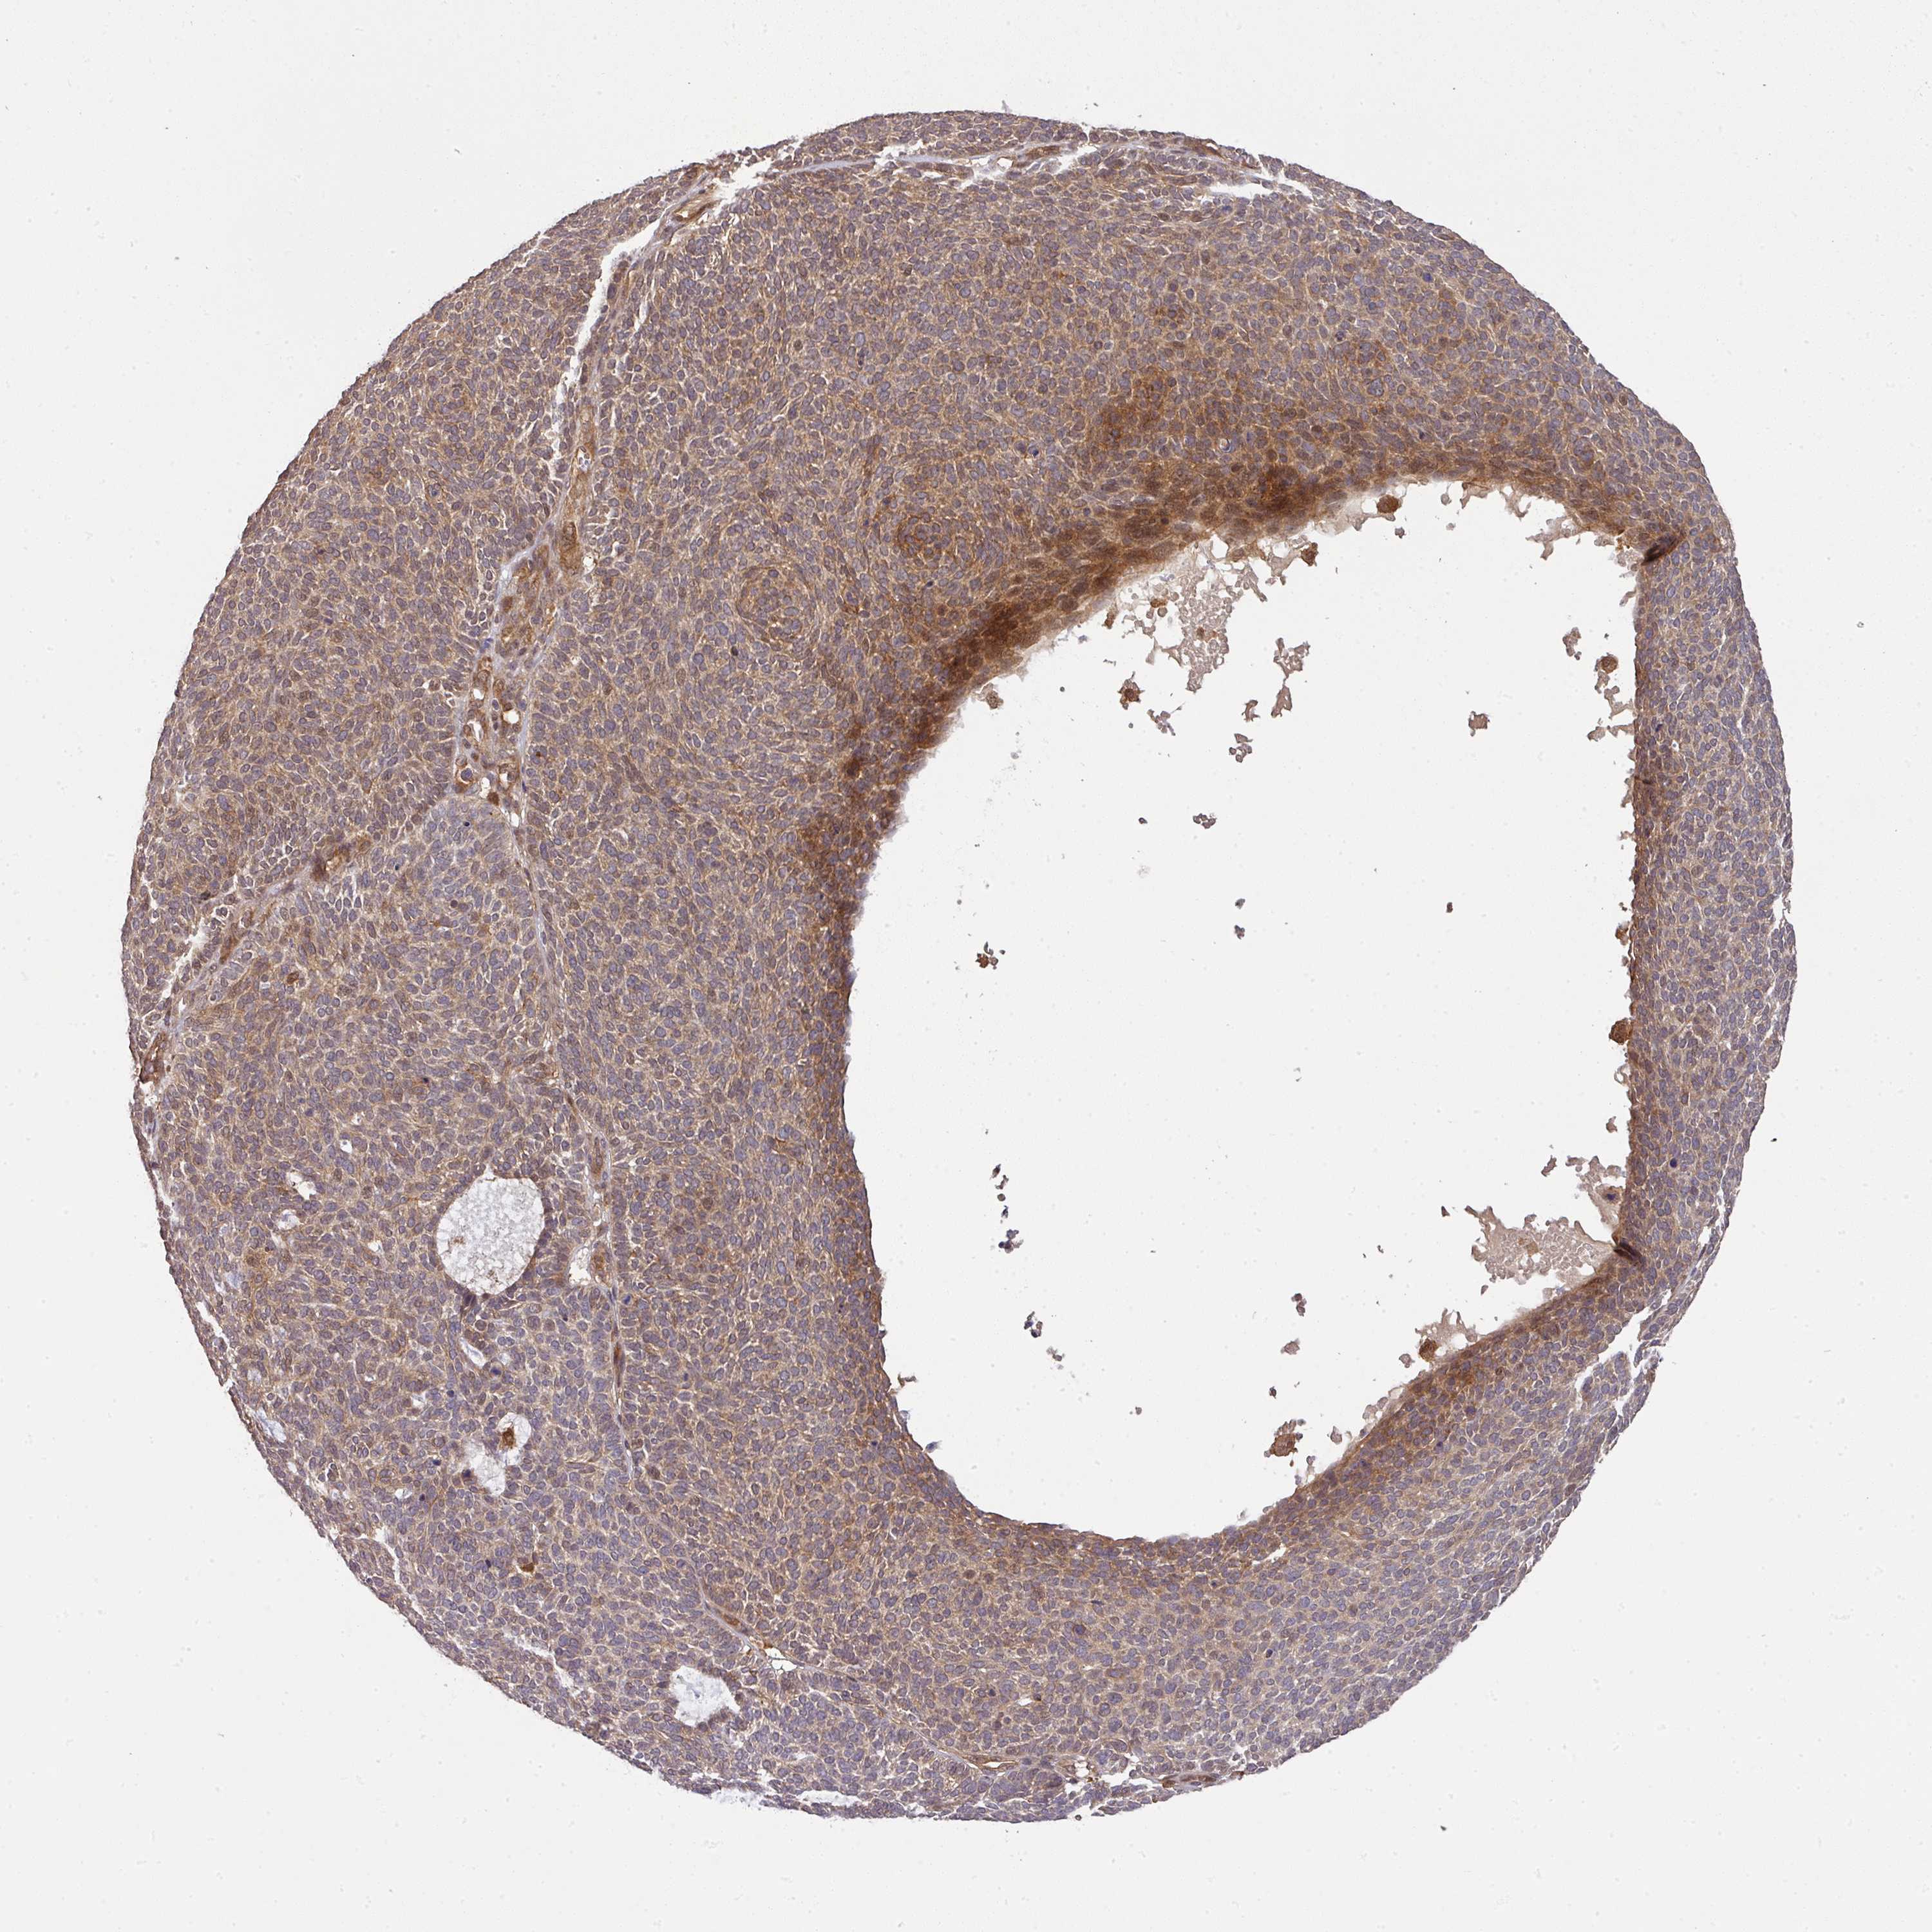

Basal cell and squamous cell cancer

SKIN CANCER - Protein expressioni

A mouse-over function shows sample information and annotation data. Click on an image to view it in a full screen mode. Samples can be filtered based on level of antibody staining by selecting one or several of the following categories: high, medium, low and not detected. The assay and annotation is described here.

Antibody stainingi

Antibody staining in the annotated cell types in the current human tissue is reported as not detected, low, medium, or high, based on conventional immunohistochemistry profiling in selected tissues. This score is based on the combination of the staining intensity and fraction of stained cells.

Each image is clickable and will lead to virtual microscopy that enables deeper exploration of all samples and also displays staining intensity scores, fraction scores and subcellular localization as well as patient and tissue information for each sample.

Squamous cell carcinoma, NOS